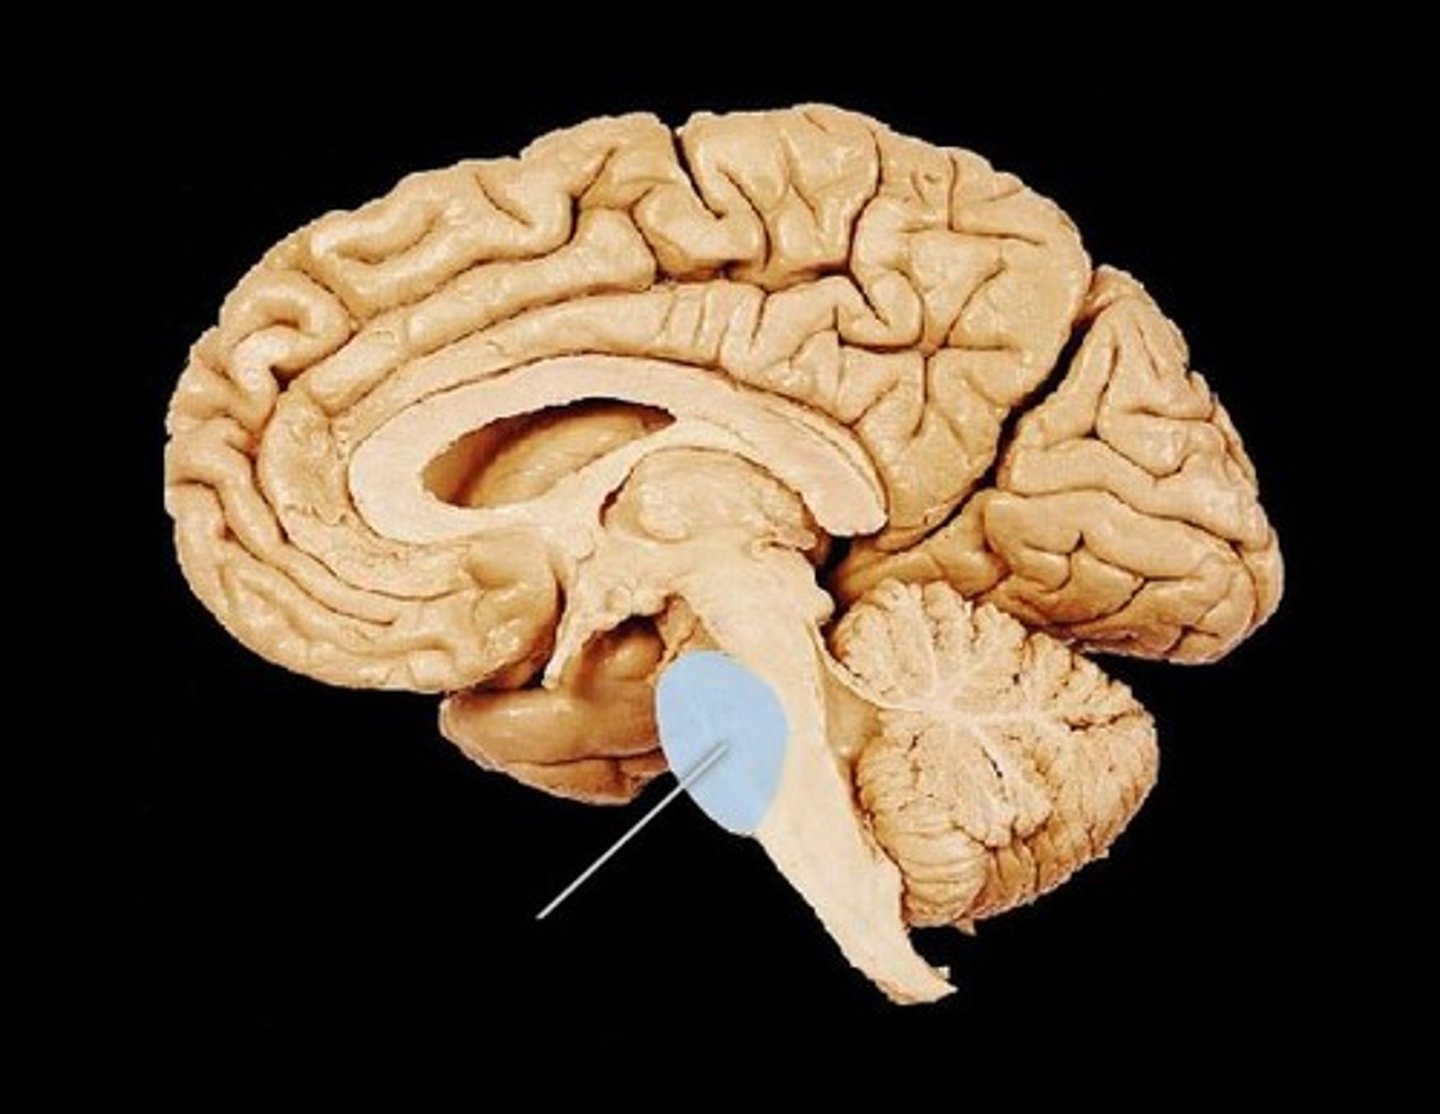

pons

Pituitary Gland

Fourth Ventricle

Hypothalamus

Medulla Oblongata